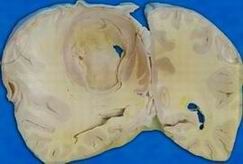

5.病理改變原發性肺炎克雷白桿菌肺炎多以大葉分布,常見於肺上葉,尤其是右上葉;繼發性肺炎多以小葉分布,為雙肺斑片樣支氣管肺炎樣表現,多肺葉、雙側性及小葉分布者少見,總體病理與肺炎球菌肺炎相似,但發展較快,無明顯肺炎的階段性變化,但有其自身特點:①屍檢病變肺葉,其切面可見到黏液樣滲出物流出,或可以挑起黏稠的絲狀滲出物,這是其病理的特徵性改變。②肺組織破壞迅速,4天之內可形成多發性膿腫或單一大膿腫,肺泡壁破壞,致肺泡萎縮,肺容積減小,主要肺血管可發生栓塞,引起繼發性肺壞疽、壞死。③常合併胸膜侵犯,發生胸膜纖維素性滲出,粘連,其發生率約為25%,甚至合併心包積液。④早期組織學檢查中,可見到水腫液、單核細胞及細菌,後期可見肺泡壁破壞,有大量多形核中性粒細胞,纖維組織增生活躍,易發生機化改變。⑤可致肺內出血、膿氣胸、心包炎、支氣管擴張等改變,部分可成為慢性克雷白桿菌肺炎變化。